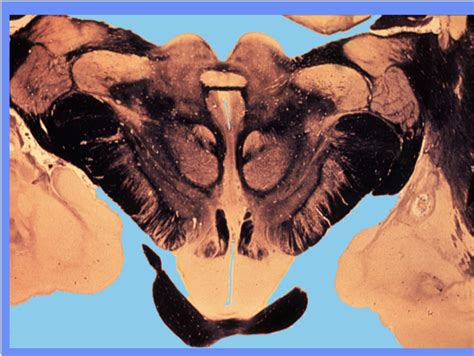

The spine’s curvature—lordotic in the cervical and lumbar regions, kyphotic through the thoracic—serves as a biomechanical masterpiece. Its alignment along the body’s vertical axis governs load distribution, spinal cord protection, and postural stability. The L4-L5 intervertebral disc, often a source of lower back pain, sits at the optimal level where compressive forces peak; misalignment here shifts stress to adjacent segments, accelerating degeneration.

Beyond static alignment, the spine’s *segmental* positioning—each vertebra’s interplay with vertebral bodies, facet joints, and ligamentous complexes—dictates nerve root function. A single misaligned vertebra, such as a subluxation at C5, can impinge on the cervical spinal nerve, triggering pain, numbness, or motor deficits. Modern imaging reveals that optimal spinal positioning preserves intervertebral hydration and disc height—critical for shock absorption in high-impact activities.

Hidden mechanics: The vertebral canal’s 12-degree anterior tilt, combined with the sacrum’s 25-degree angle relative to the pelvis, creates a neutral zone that shelters the spinal cord from vertical shock. This alignment is not fixed—it adapts subtly to movement, with intravertebral discs shifting up to 3 millimeters during flexion.